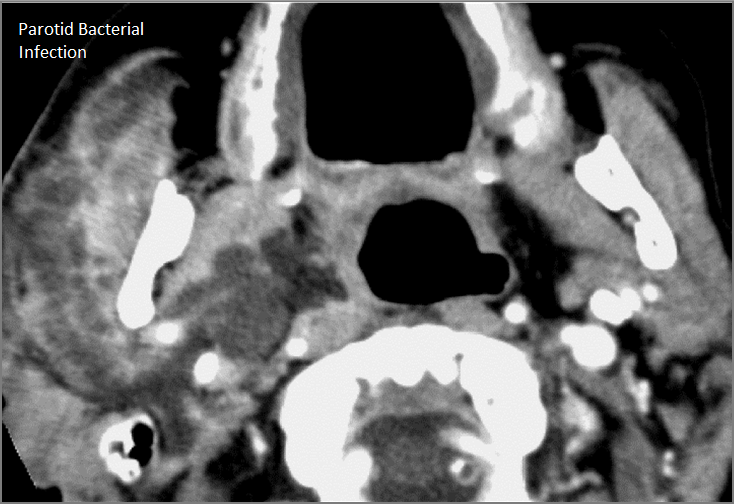

Major Salivary Glands

There is significant abnormality of the parotid, submandibular or sublingual glands that would be an alternate explanation for the patient’s symptoms.